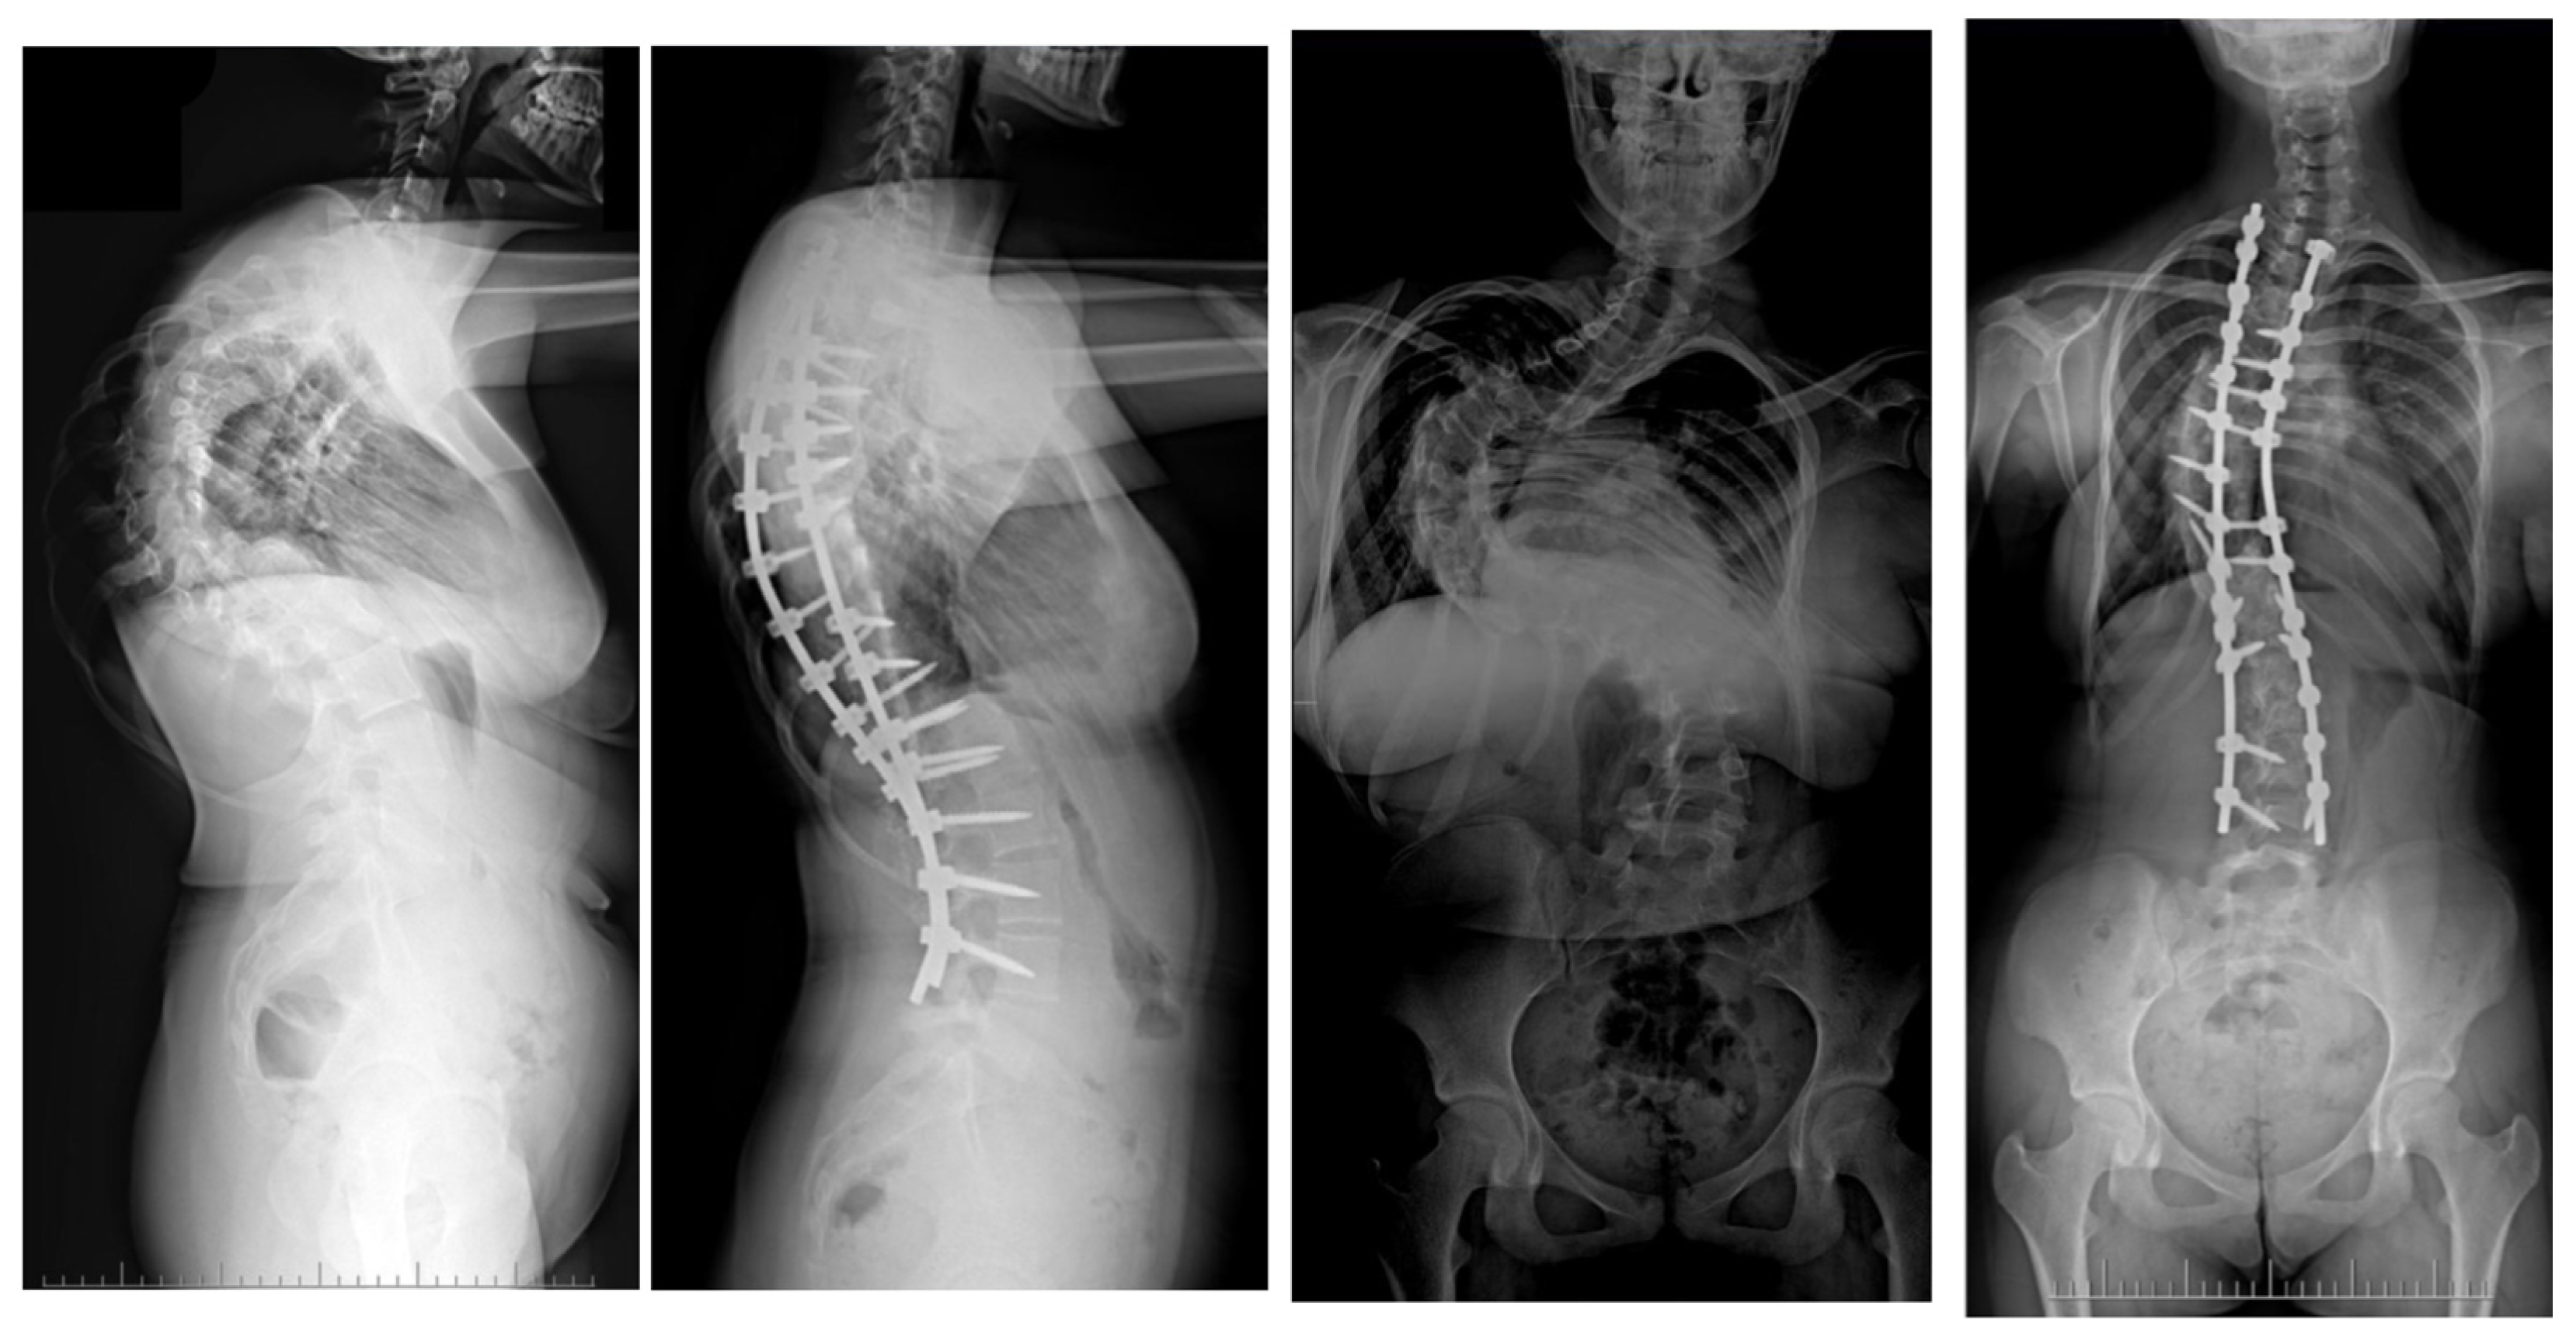

Large spinal deformities, especially those originating from underlying neuro-muscular conditions or severe lumbar scoliosis, can pose a significant challenge when it comes to dealing with pelvic obliquity [62,63]. The presence of pelvic obliquity can lead to incorrect sitting posture and persistent pressure ulcers, making it a crucial issue to address for achieving a positive outcome; nevertheless, it is a task that is often intricate and multifaceted [63]. In the realm of addressing pelvic obliquity, intraoperative halo traction (HT) emerges as a valuable adjunct for improving the correction of this condition. A research study involving a cohort of 40 patients with neuromuscular scoliosis who underwent posterior spinal fusion with an extension of fixation to the pelvis highlighted that 20 of these patients were subjected to intraoperative HT [62]. The initiation of HT took place subsequent to the induction of anesthesia, with each halo being firmly secured by four pins. Following this, a sturdy Kirschner wire was carefully inserted through the distal femur on the side exhibiting the elevated hemipelvis. Upon assuming the prone position in the conventional manner, a traction of 6.8 kg was applied to the halo, which was then gradually escalated to an average of 11.3 kg until the pelvis achieved the desired alignment. The outcomes of this intervention indicated a notable 78% correction in pelvic obliquity within the HT group, in contrast to 52% in the control group [62]. Similarly, a detailed case report by Huang et al. illustrated the successful rectification of severe pelvic obliquity through the implementation of intraoperative HFT [63]. A separate study by Hamzaoglu et al. delved into the cases of 15 patients with thoracic scoliosis who underwent a treatment regimen involving intraoperative HFT in conjunction with posterior-only instrumentation [58]. Unlike prior analyses, HFT was not specifically employed for addressing pelvic obliquity in this scenario. The established protocol entailed obtaining a pre-operative traction radiograph while the patient was under anesthesia, resulting in an average enhancement of 51% in the major thoracic curve. In instances where the curve did not exhibit adequate correction, extensive facet resection and posterior release procedures were carried out. Noteworthy investigations focusing on intraoperative HFT have not documented any complications linked to traction [59]. Owing to the transient nature of the traction utilized, issues commonly associated with pre-operative traction, such as infections at the pin sites or loosening, are anticipated to be less prevalent in occurrence. Barsoum et al. chronicled a case involving an adult patient who was subjected to 2.3 kg of traction using Gardner-Wells tongs, and subsequently experienced a post-operative cranial nerve VI palsy [61]. However, reassuringly, this neurological impairment was completely resolved during the 6-month follow-up evaluation. Figure 4 shows X-rays of a 14-year-old girl treated with intraoperative halo-femoral traction.

Figure 4.

Radiographs taken before and after surgery at the last follow-up appointment depicting a 14-year-old female with severe adolescent idiopathic scoliosis who underwent intraoperative halo-femoral traction, followed by multi-level Ponte osteotomy and posterior spinal fusion in a single-stage surgical procedure.